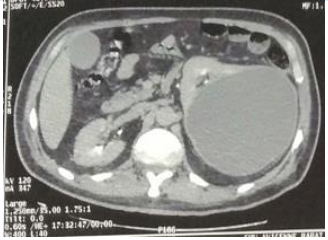

Despite 48 hours of antibiotic treatment, there was no clinical or biological improvement. A contrast-enhanced abdominal and pelvic CT scan (excretory phase) confirmed the findings without providing further diagnostic clarity (Figures 1 and 2)

Figure 2: Coronal section from a delayed-phase abdominal CT scan showing a 17 cm renal cyst with contrast-enhancing wall and hypodense content. No communication was observed between the cyst and the pelvicalyceal system.